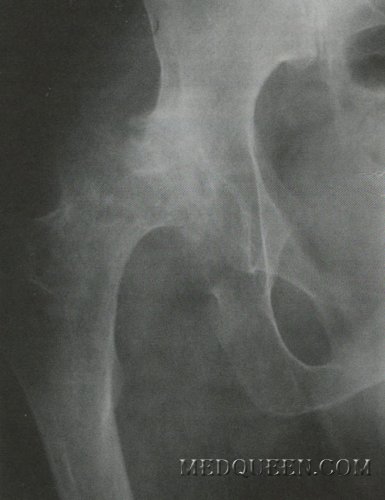

Комбинированное поражение костей таза у больного гемофилией А

У больного отмечены неоднократные кровотечения в суставы, а также кровотечения после незначительных травм. Комплексное поражение суставов нижних конечностей с анкилозированием диагностировано в 6-летнем возрасте, в тоже время была проведена хирургическая репозиция суставов. С 10 до 19 лет заболевание имело стабильное легкое течение. Ухудшение состояния (повышение частоты гемартрозов, которые появлялись спонтанно и сопровождались стабильным ухудшением функции суставов с выраженными общими воспалительными процессами) отмечено в 19 лет. учитывая этот фактор к заместительной терапии были назначены селективные ингибиторы ЦОГ-2 и глюкокортикостероиды. Данная терапия способствовала снижению выраженности симптомов воспаления, но через год пациент начал жаловаться на боль в костях, особенно в бедренных и тазовых. Результаты исследования показали остеопороз, при этом были назначены препараты кальцитонина, бисфосфонаты, но остеопоротические изменения костей продолжали прогрессировать, появились признаки двустороннего коксартроза.

У данного пациента многочисленные кровотечения в хрящ спровоцировали трофическое поражение костей, а терапия глюкокортикостероидами усилила катаболические процессы в костной ткани. Повторные кровотечения сформировали так называемый замкнутый круг патологического поражения и привели к выраженной деструкции тазовых костей и тазобедренного сустава (см. фото).

Хирурги-гематологи нескольких украинских научно-исследовательских институтов патологии крови и трансфузионной медицины, которые консультировали больного, пришли к выводу, что протезирование сустава не рекомендовано из-за диффузного остеопороза тазовых костей.